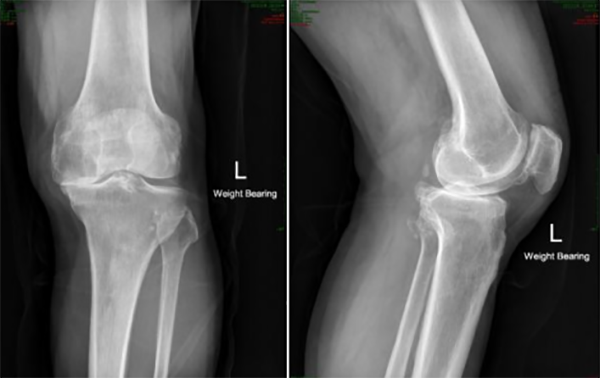

▲術前影像